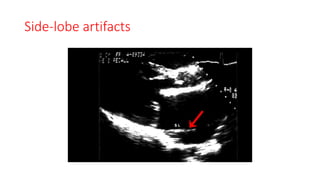

Side-lobe artifacts

• The assumption that the ultrasound waves are infinitely thin is

violated.

• Side and grating lobes are secondary beams around the central

ultrasound beam and are produced by nonaxial vibrations of the

piezoelectric elements.

• it can be difficult to differentiate between side and grating lobe

artifacts.

• Differential diagnosis for masses in the left atrial appendage.

• Side-lobe–generated artifacts may contribute to making normal,

stented bioprosthetic aortic valve appear abnormally bent.